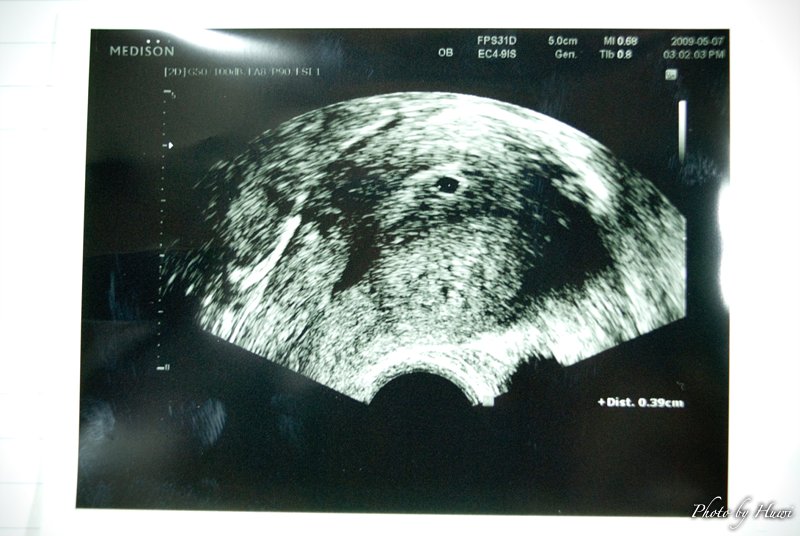

3~4주 정도 된것 같다고 합니다..

날짜 계산해보니 허니문 베이비인듯 하군요..

이제 12주째야..허니문 베이비라네..ㅎㅎ